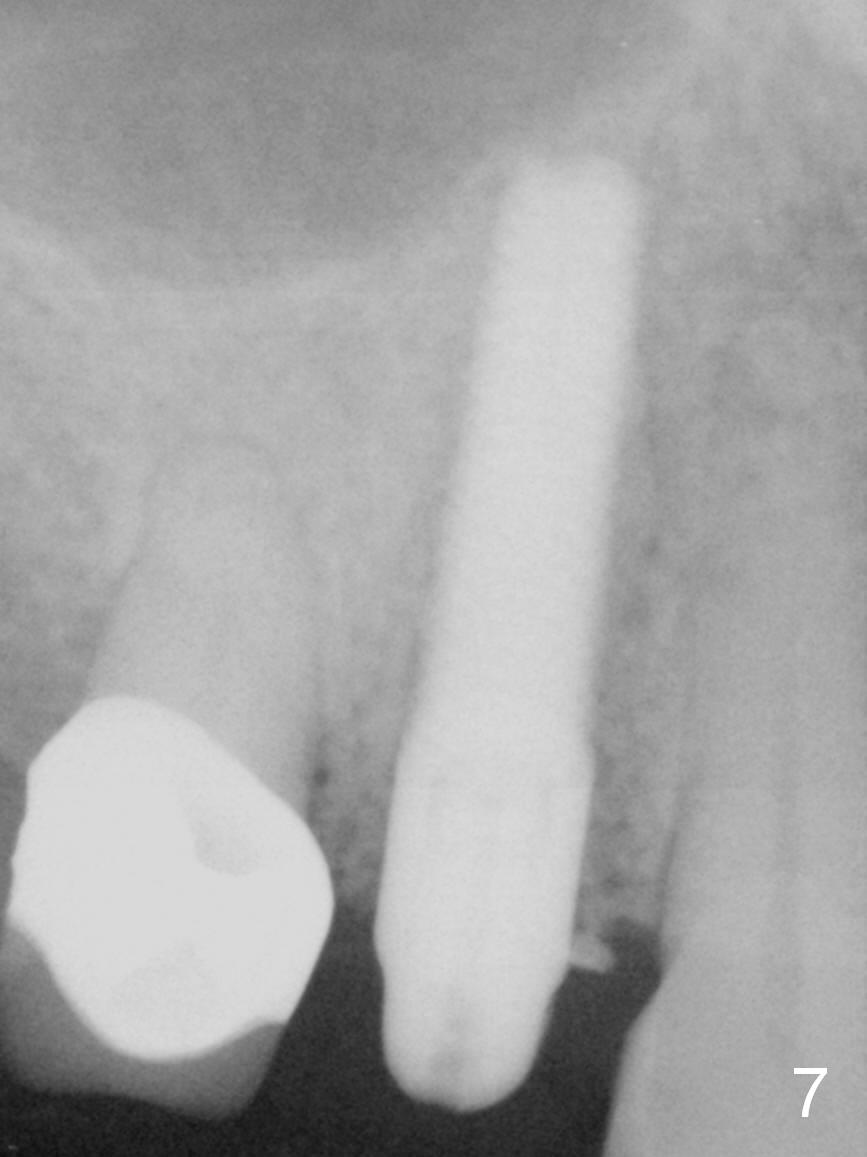

After long discussion, she agrees with extraction and immediate implant. After the extraction, granulation tissue is removed. There is buccal apical fenestration. The socket is treated with Metronidazole. The socket depth is 17 mm, while osteotomy depth is 20 mm (Fig.4). A 4x20 mm tissue-level implant is placed with primary stability (Fig.5,6 I). A short abutment (A) is placed immediately for an immediate provisional. The buccal gap is filled with Osteogen plug. There is no crestal bone loss 3 months postop (Fig.7). The provisional stays in place with occlusal perforation. The gingiva is healthy 5.5 months post cementation (Fig.8).